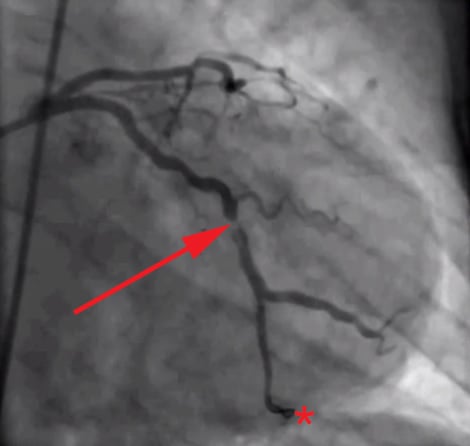

The root of the problem, in my view at least, is that we as doctors—and by extension, our patients and media—spend too much time looking at images like this (angiograms of coronary arteries complete with “clogged pipes”):

And not enough time looking at images like these (the histological, i.e., pathology, sections of coronary arteries):

But who can blame us, I mean, angiograms are cool! But, alas, it’s time to get serious about understanding this disease if we want to prevent/delay it.